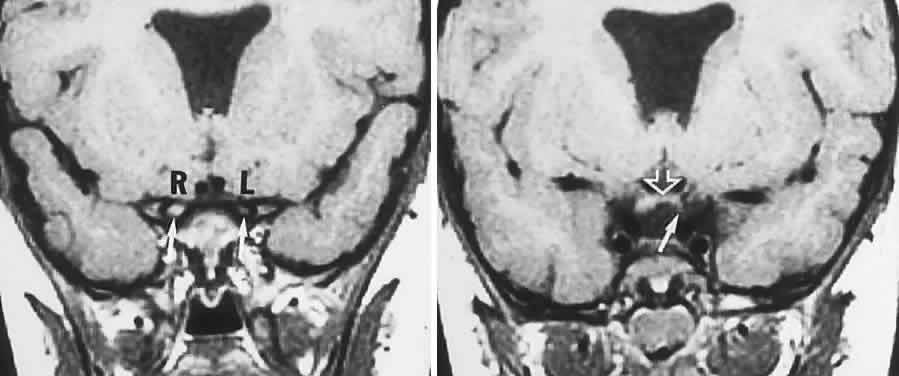

Back to Top